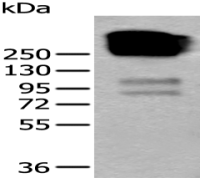

Immunohistochemistry

Predicted cell location: Nucleus

Positive control: Human lung cancer

Recommended dilution: 30-150 Predicted cell location: Nucleus

The image on the left is immunohistochemistry of paraffin-embedded Human lung cancer tissue using ml224923(BCAS3 Antibody) at dilution 1/35, on the right is treated with fusion protein. (Original magnification: ×200) The image on the left is immunohistochemistry of paraffin-embedded Human colorectal cancer tissue using ml224923(BCAS3 Antibody) at dilution 1/35, on the right is treated with fusion protein. (Original magnification: ×200)